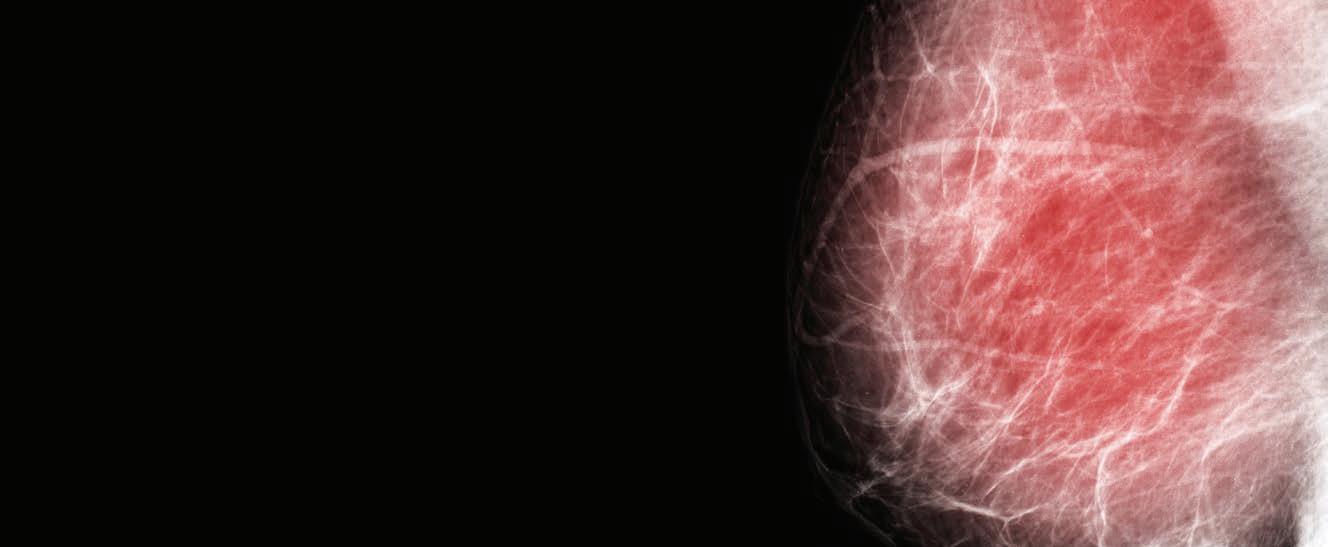

Keeping abreast of cancer care

With GPs recently updated on the prevention and early detection of breast cancer, debate about how to manage breast density has come under the spotlight once again.

The statistics for breast cancer in Australia are sobering. Not only is it the most common cancer in women – responsible for more than 21,000 new cases a year – it is also the second leading cause of death.

The lifetime risk of the disease is now nudging one in seven for women by the age of 85 – compared to about one in 12 in the 1990s – and there has been an increase in cases in younger women.

Breast density role

The latest RACGP breast cancer advice weighs into the ongoing debate about managing breast density – the proportion of fibroglandular tissue measured on a mammogram.

Dense breast tissue, like cancer, appears as white on a mammogram, making it hard to pick up cancer and potentially delaying diagnosis and resulting in more advanced cancers. It is also itself an independent risk factor for developing the disease.

Breast density is not related to breast size or the ‘breast aware’ message promoted to women because it cannot be determined by feel or touch.

About 10% of Australian women have extremely dense breasts and they are four to six times more likely to get breast cancer than those with fatty breasts.

The RACGP guidance concludes that while women with dense breasts are more likely to benefit from supplemental screening, there

is not enough evidence to routinely recommend this.

But the issue of whether women who are found to have dense breasts during their mammograms should at least be notified of this information has recently gained more clarity.

In what many doctors regard as a significant shift in position, Australia’s government-funded BreastScreen service now recommends that women with dense breasts be advised in writing and encouraged to talk to their doctor.

Western Australia has long been acknowledged as a trailblazer in this area – having quietly introduced a similar policy more than 15 years ago.